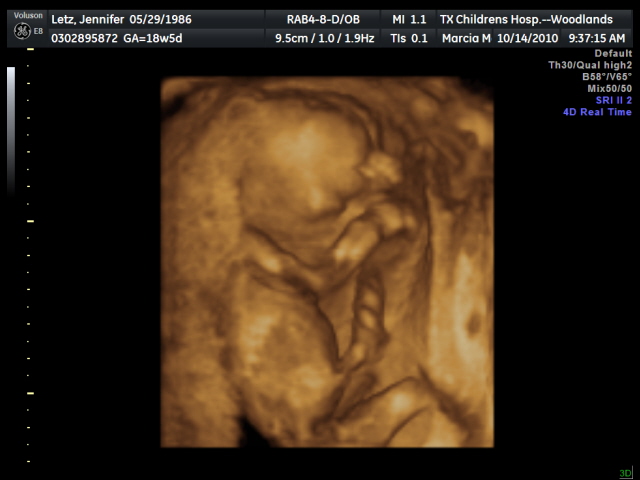

Gender? Still a baby GIRL!!

Milestones: I'm in the 3rd trimester!!! And as of today, only 87 days until Elizabeth's due date